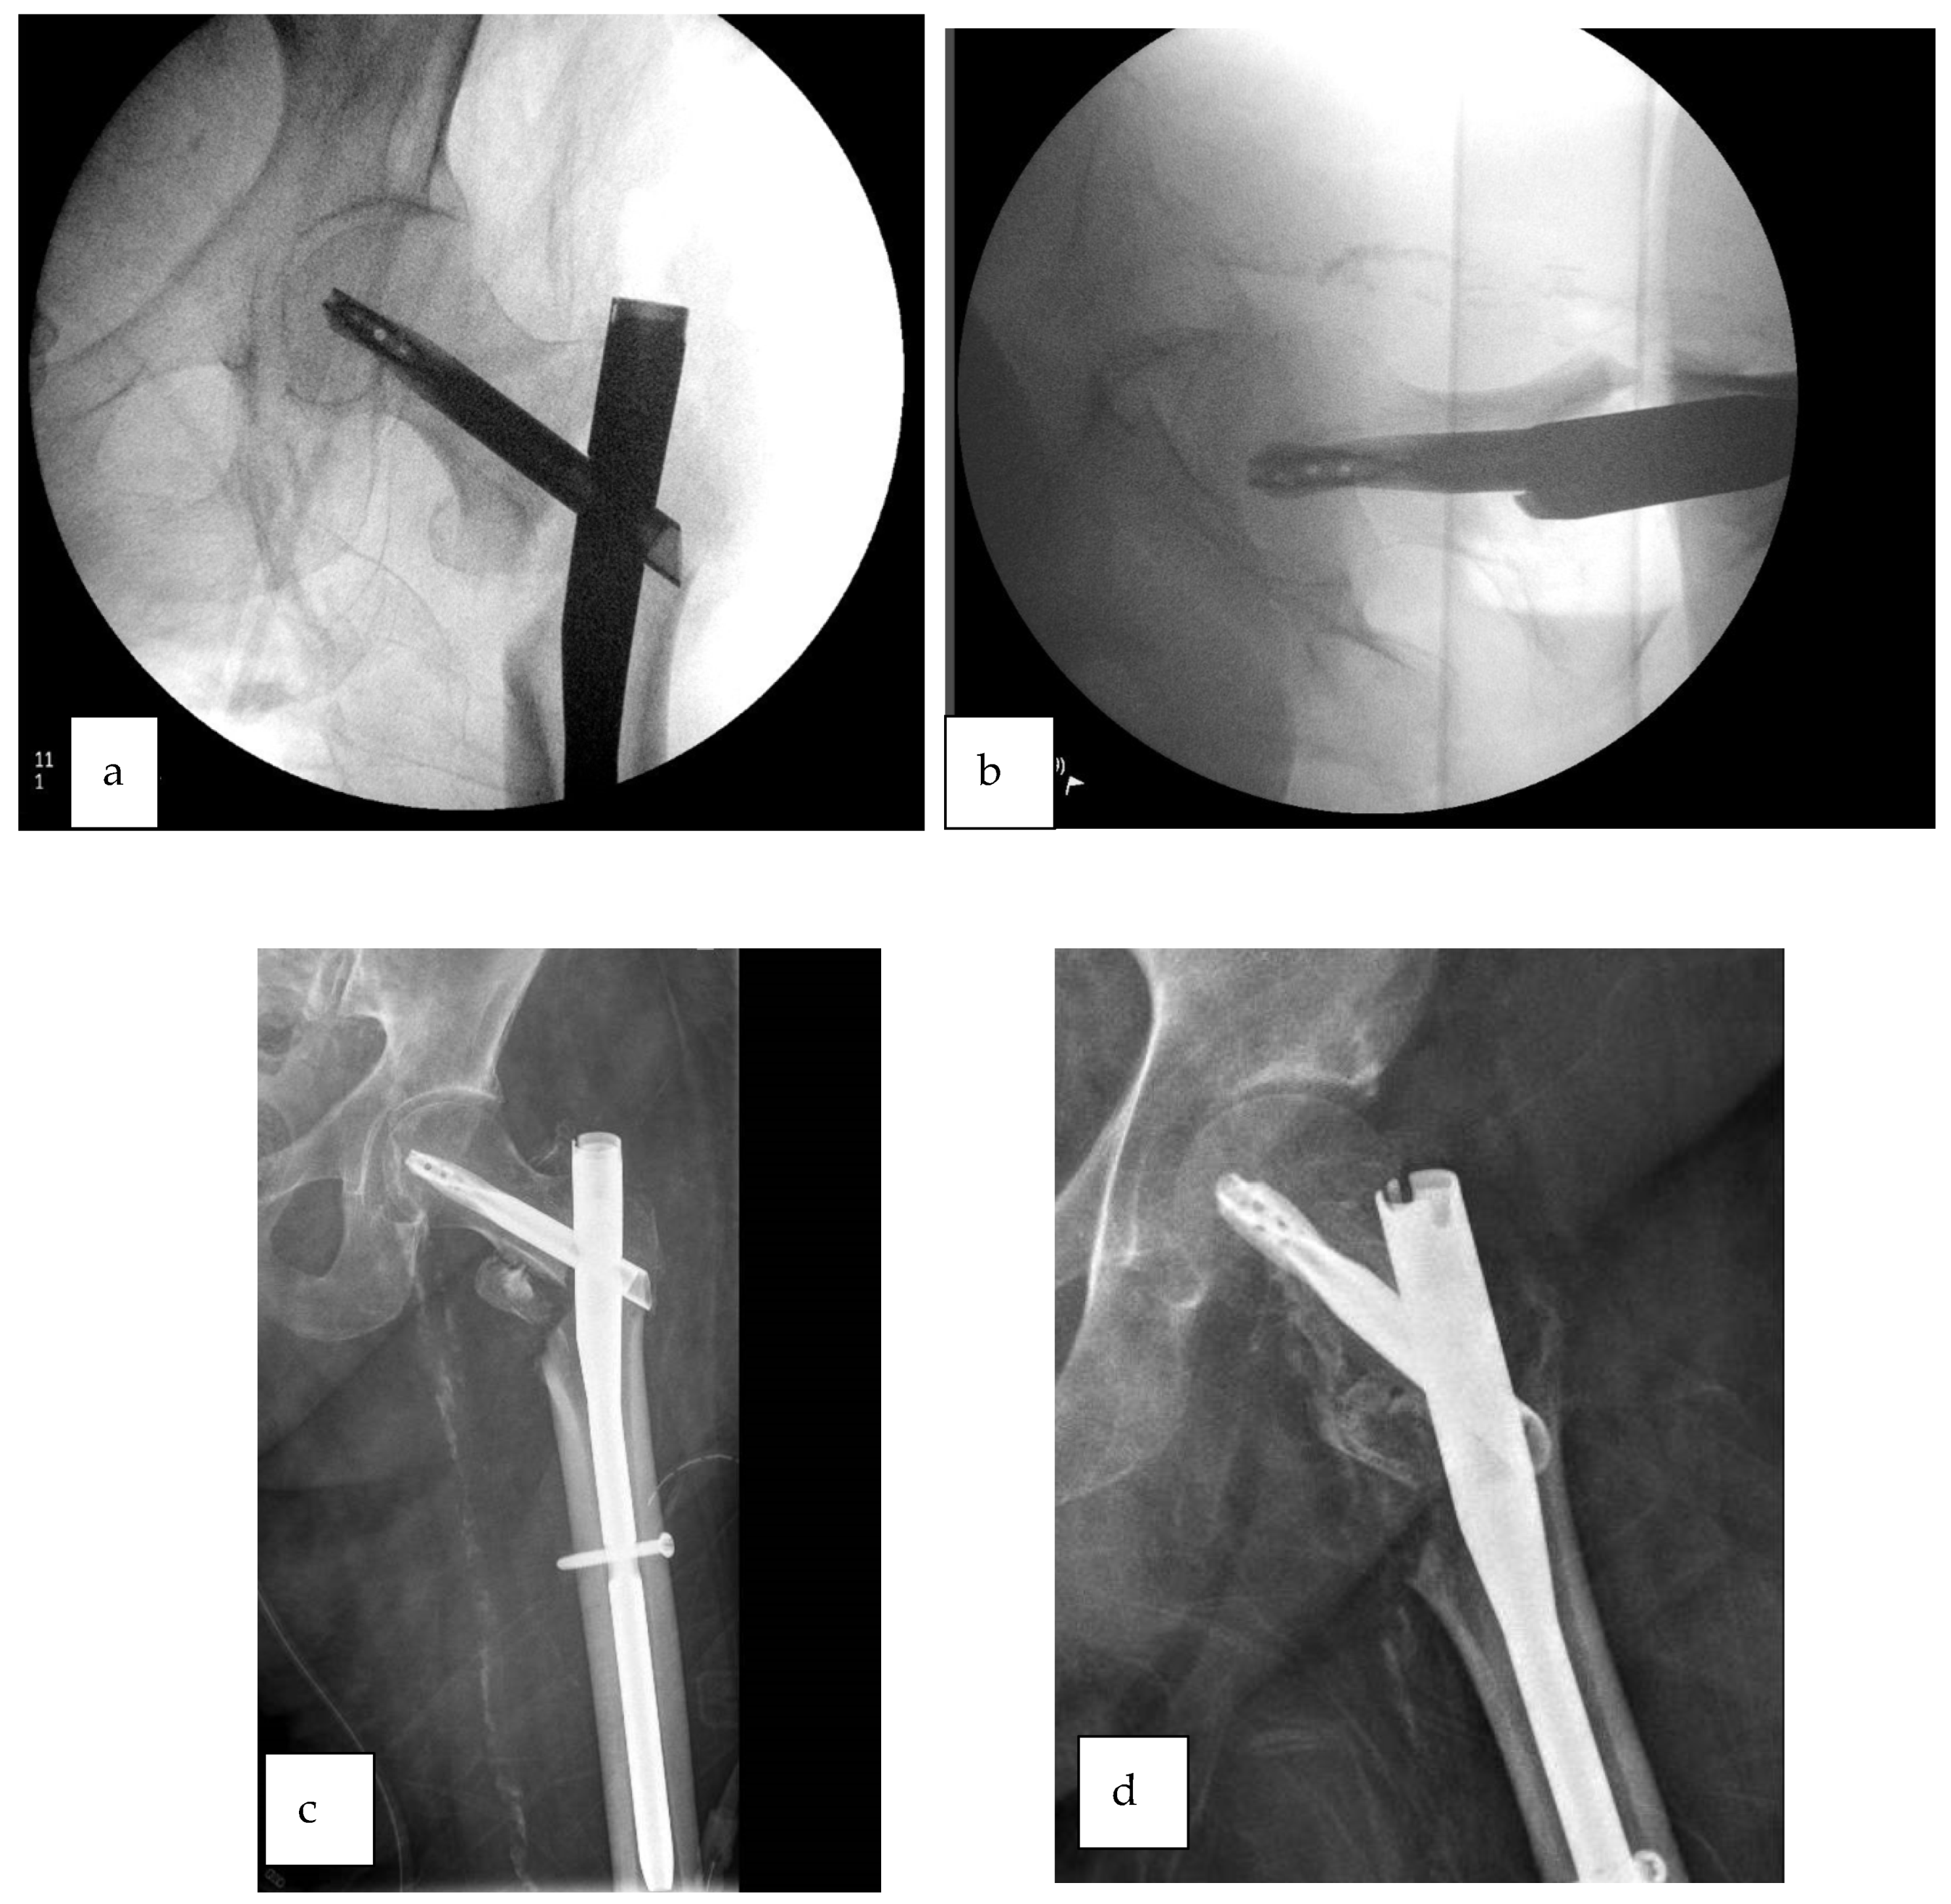

2.7.2. Case 2—Unable to Unleash Traction